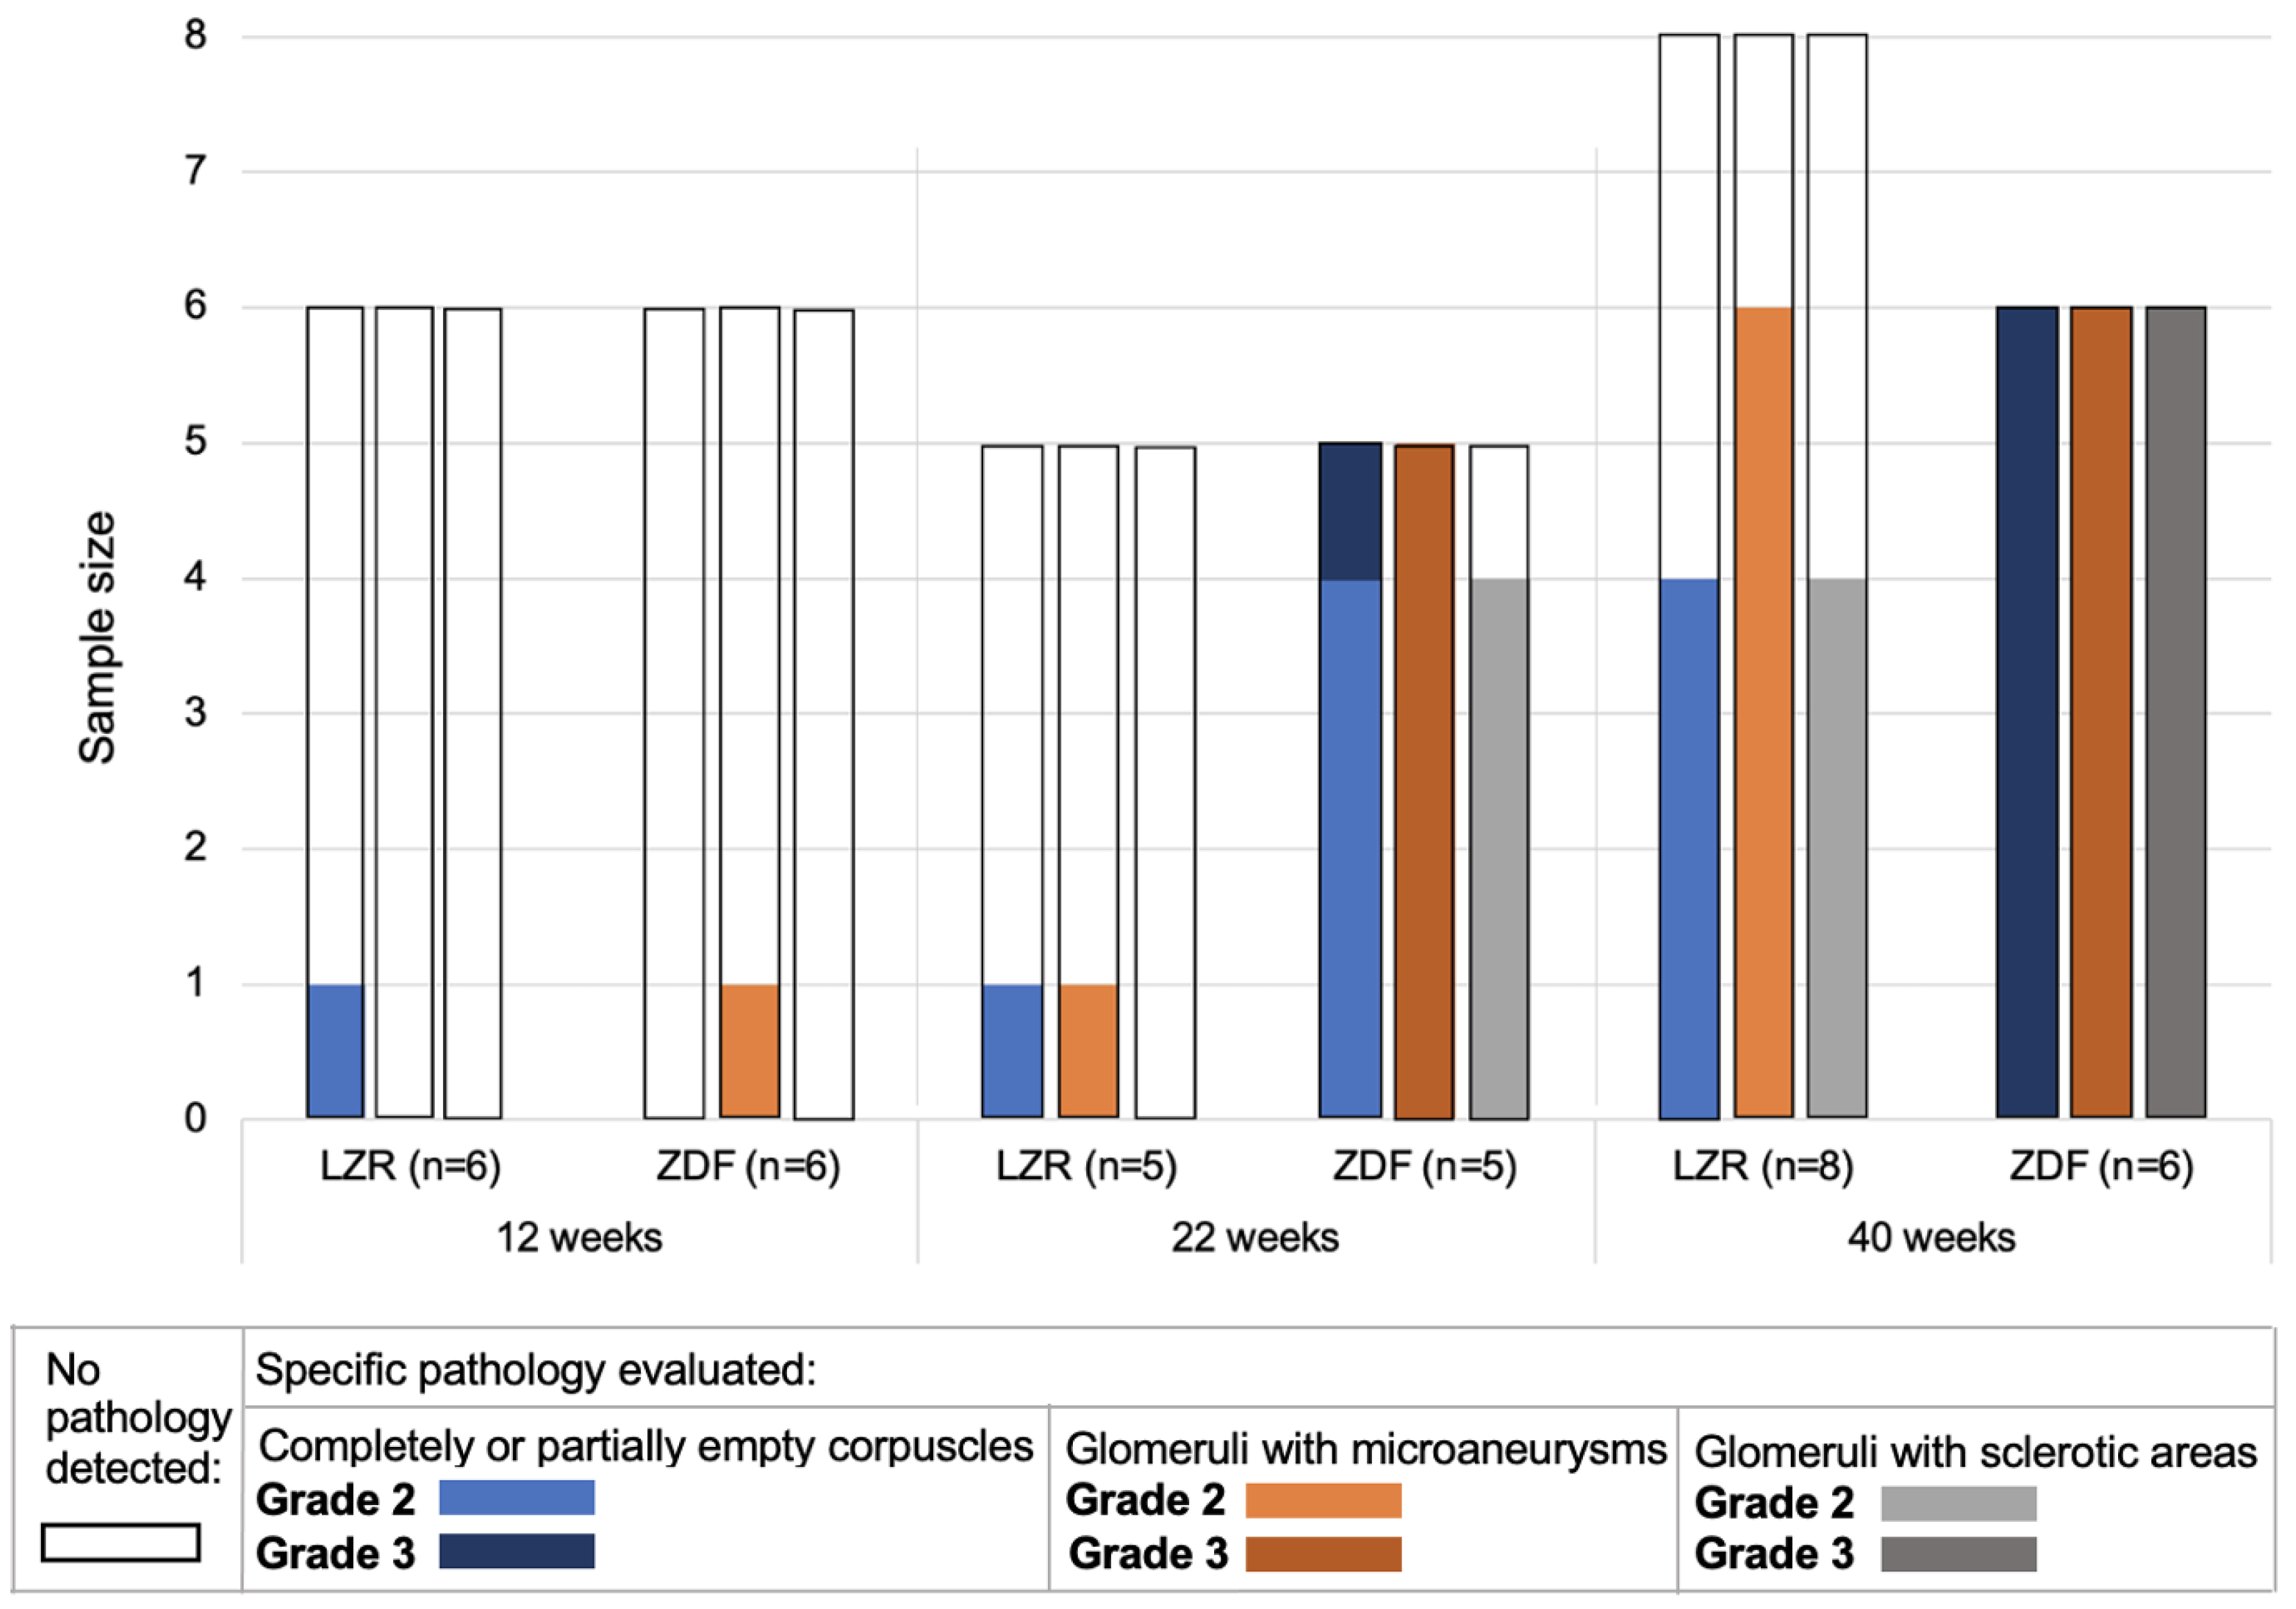

3.2. Glomerulopathy Grading

3.3. Quantified Measurements from SRUS

- Amann, K.; Haas, C.S. What You Should Know about the Work-up of a Renal Biopsy. Nephrol. Dial. Transplant. 2006, 21, 1157–1161. [Google Scholar] [CrossRef] [PubMed]